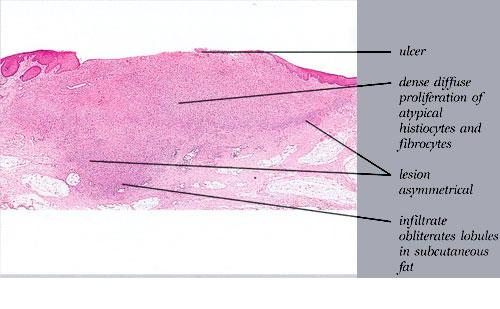

malignant-fibrous-histiocytoma